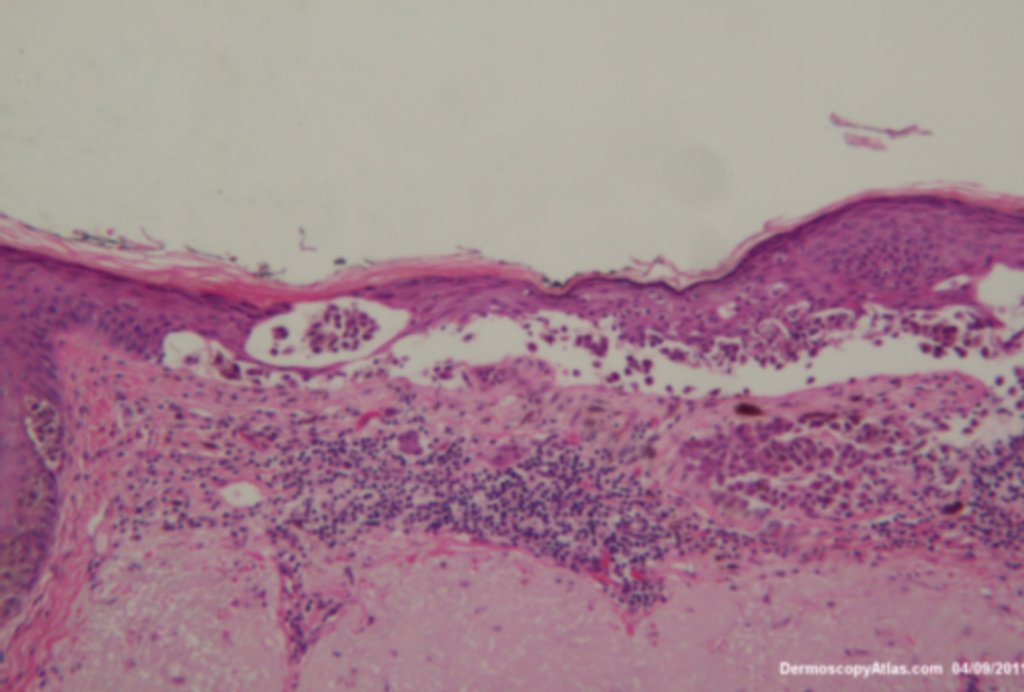

This lesion was noted fotuitously when the patient was having another procedure done on his back. Dermatoscopically it shows peripheral clods of varying sizes, multiple colours and on the enlarged dermatoscopic view some diffuse fine grey dots. It was an invasive melanoma Level 2 , 0.4mm in depth . The histology shows an unusual feature of acantholysis of the tumour nests.